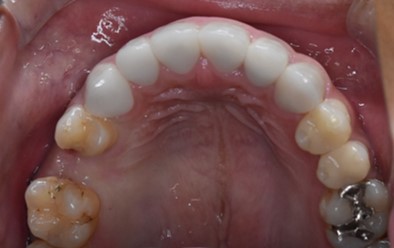

インプラント症例(20代男性)左上奥歯の治療後。隣の歯を削らず補綴した状態

Before

After